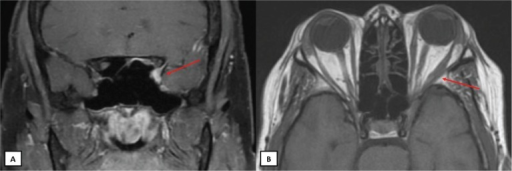

해면정맥동증후군은 해면정맥동을 통과하는 CN3, CN4, CN6, V1, V2, 내경동맥 교감신경의 다발 손상입니다.

안와첨증후군 vs 해면정맥동증후군: 안와첨 = CN2 포함(시력저하), V2 미포함. 해면정맥동 = CN2 미포함, V2 포함. CN6은 해면정맥동 내부에 있어 가장 먼저 침범됩니다.